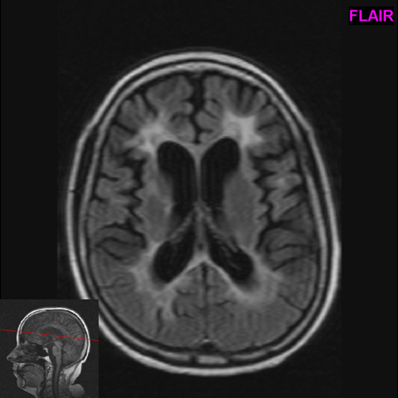

Magnetická rezonance mozku a míchy je zásadní pro diagnostiku roztroušené sklerozy. Více informací o diagnostice a léčbě rs: Magnetická rezonance a roztroušená skleróza mozkomíšní. Obvykle se používají až čtyři metody detekce roztroušené sklerózy. Základní rolí magnetické rezonance u roztroušené sklerózy mozkomíšní je stále podpora diagnózy a diferenciální diagnostika. Roztroušená skleroza a magnetická rezonance. V práci je shrnut přehled měnících se mr kritéri í a srovnání jejich výtěžnosti. Léčení vyžaduje, aby postižení přestali jíst maso, mléčné výrobky a veškeré potraviny bohaté na nasycené tuky. Roztroušená skleróza je autoimunitní onemocnění. Rýchlosť stanovenia diagnózy roztrúsenej sklerózy. Et al., roztroušená skleróza v praxi, galén, praha 2015.» Při zjišťování rs magnetickou rezonancí dochází k sledování toho, zda proběhla demyelinizace nervových vláken. Magnetická rezonance je nejdůležitější z podpůrných vyšetřovacích metod pro di agnostiku rs.

Pri nákupe nad 49 € máte poštovné zadarmo. Let minulého století umožňuje zobrazit i drobná zánětlivá ložiska. Rýchlosť stanovenia diagnózy roztrúsenej sklerózy. Podívejte se na jejich rady a přidejte do diskuze své zkušenosti. Et al., roztroušená skleróza v praxi, galén, praha 2015.» Roztroušená skleróza propuká nejčastěji mezi 20 a 40 rokem života. Rychlost stanovení diagnózy roztroušené sklerózy, pro niž je magnetická rezonance zásadním přínosem, se stává stále naléhavější kvůli včasnému zahájení adekvátní léčby, neboť je známo, že její oddálení vede k nevratnému poškození pacienta. Roztroušená skleróza neboli mnohotná skleróza je chronickým autoimunitním onemocněním nervového systému. Špatnou zprávou pro ženy je, že právě ony trpí touto nemocí častěji. Roztroušená skleroza a magnetická rezonance. Kromě magnetické rezonance jsou dalšími používanými diagnostickými nástroji analýza mozkomíšního moku. Přesná diagnóza se získá magnetickou rezonancí (ct je nedostačující) a vyšetřením mozkomíšního moku (lumbální punkcí). Vyšetření mozku funkční magnetickou rezonancí (fmri) slouží nejen k určení jeho anatomických struktur, ale je také schopné dát…

Rychlost stanovení diagnózy roztroušené sklerózy, pro niž je magnetická rezonance zásadním přínosem, se stává stále naléhavější kvůli včasnému zahájení. Mozek a nervy lucie 30.4.2017. Let minulého století umožňuje zobrazit i drobná zánětlivá ložiska. Zákeřné chronické autoimunitní onemocnění nervového systému, jehož prvotní příznaky se začínají objevovat nejčastěji u mladých dospělých lidí, častěji u žen než u mužů. Magnetická rezonance poskytne trojrozměrné obrazy orgánů a struktur bez vyzařování rentgenových paprsků. Magnetická rezonance a roztroušená skleróza mozkomíšní. Jedná se o moderní diagnostickou metodu sloužící k detailnímu zobrazení tkání lidského těla. Zde je poradna o tématu: